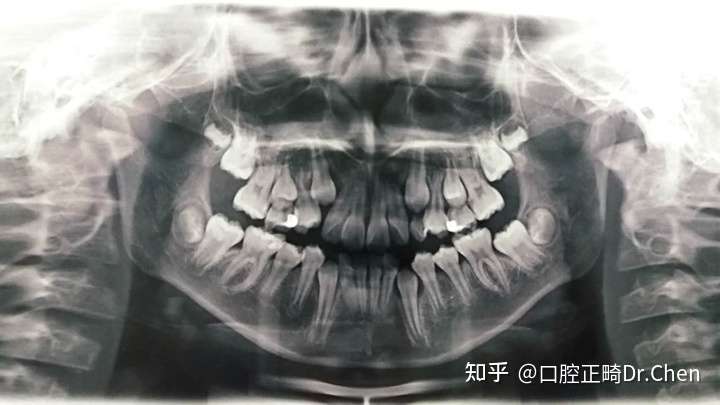

口腔全景片看分解图

口腔全景片看分解图,口腔全景片解剖结构

口腔全景片

口腔牙齿发育全景片

口腔全景片解剖结构

新手看口腔全景片图解

口腔全景片图解

口腔全景片解剖图解

口腔全景片图片

儿童口腔全景片